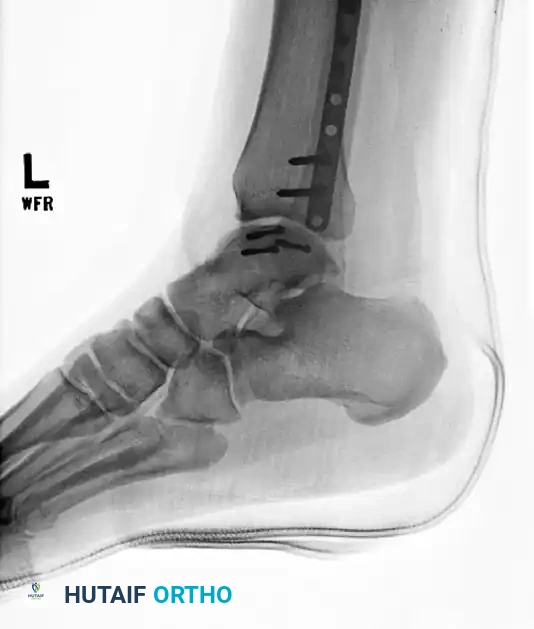

FIGURE 88-42 A: Preoperative radiograph demonstrating a severe talar body fracture with an associated fibular fracture, a classic injury pattern that, if unsalvageable, may necessitate tibiocalcaneal arthrodesis.

FIGURE 88-42 C: Concurrent fixation of the fibula with a neutralization plate and screws. Failure of such constructs often leads to the salvage pathways discussed herein.